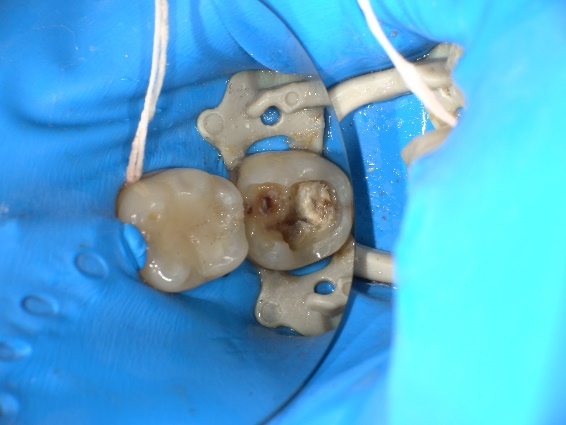

| 院長コメント | ①むし歯を治療して歯を型どりする時 ②ジルコニアを歯と接着させる時 唾液を極力排除する必要があります。ラバーダムというゴムの膜を用いて歯を唾液から隔離します。今回はかぶせ物(クラウン)の形で接着面全周をラバーダムの上に出すのはかなり難しかったのですが、工夫をすることで接着面全てをラバーダムの上に設置することができ、接着力を最大限に発揮できました。 |